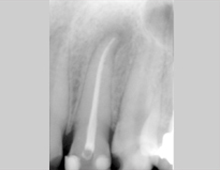

Bei der Wurzelbehandlung wird der Zahn unter örtlicher Behandlung aufgebohrt und der erkrankte oder abgestorbene Zahnnerv entfernt. Anschließend wird der Wurzelkanal gereinigt, desinfiziert und mit einer Wurzelfüllung versorgt. Das Pulpa-Füllmaterial zeichnet sich durch höchste Gewebefreundlichkeit und Volumenstabilität aus.

Mit der vollständigen Füllung des Wurzelkanalsystems ist eine Wurzelbehandlung jedoch noch nicht abgeschlossen. Durch die Entfernung des Nervengewebes ist der Zahn nun nicht mehr versorgt und wird – ähnlich einem abgestorbenen Baum – spröde und brüchig. Um die Kaukräfte gleichmäßig auf den Zahn zu verteilen und somit ein Brechen des Zahnes zu vermeiden, sollte ein wurzelbehandelter Zahn mit einer Krone versorgt und geschützt werden.